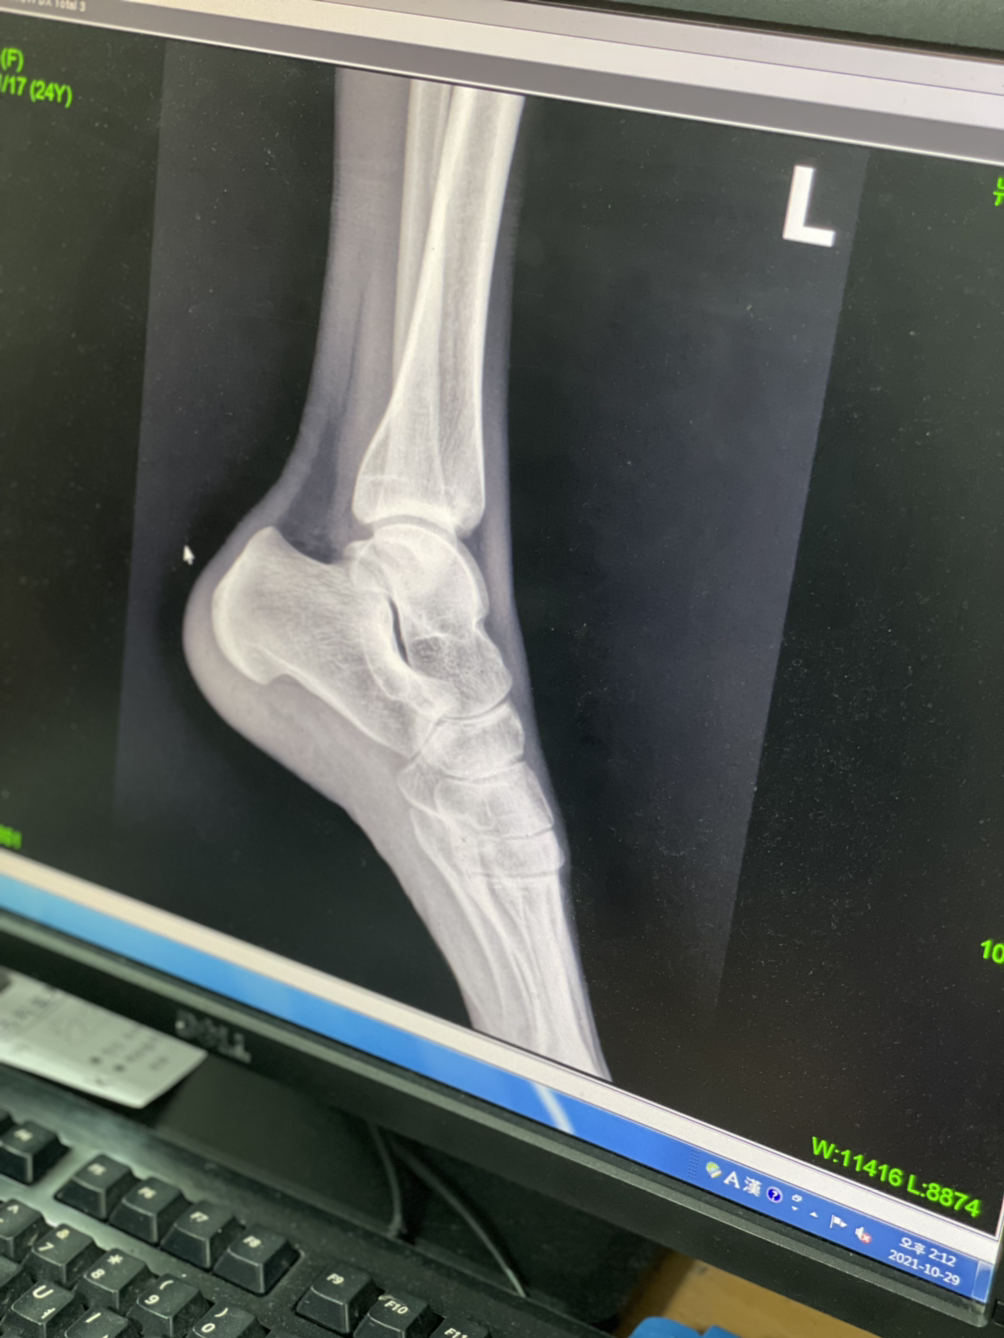

아플땐 쉬어가자 ㅎ ..아킬레스건염이라네..^^..

골반이 삐뚤어졌대

종형외과...

넘비싸...8ㅅ8 근데 너무아프고...ㅋㅋㅋ 많이 삐둘어지긴한듯